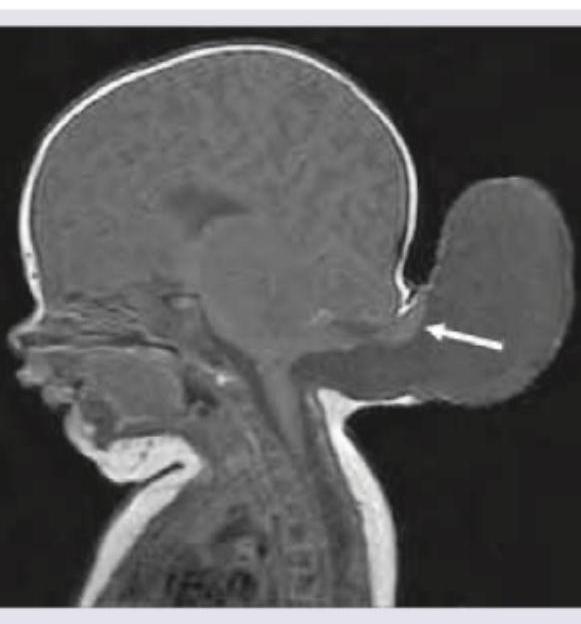

The image shows presence of:

Explanation: ***Correct: Encephalocele*** The image clearly shows an **extrusion of brain tissue and meninges through a defect in the skull**, particularly in the occipital region, which is characteristic of an encephalocele. The arrow points directly to this **sac-like protrusion of brain material** extending beyond the normal skull contour. This represents a neural tube defect where the cranial bones failed to close completely during development, allowing brain tissue to herniate through the defect. *Incorrect: Holoprosencephaly* Holoprosencephaly is characterized by a **failure of the prosencephalon to cleave into two cerebral hemispheres**, resulting in a single ventricular cavity and associated facial anomalies. This is an **internal structural abnormality** affecting brain division and differentiation, not an external protrusion. The image does not show incomplete hemispheric separation or midline fusion defects. *Incorrect: Anencephaly* Anencephaly is a severe neural tube defect characterized by **absence of a major portion of the brain, skull, and scalp**. In anencephaly, the cranial vault is largely absent with exposed, rudimentary brain tissue. The image shows a **substantially intact cranial cavity with normal brain tissue** and an external sac, which is completely different from the massive tissue absence seen in anencephaly. *Incorrect: Dandy-Walker syndrome* Dandy-Walker syndrome involves a **malformation of the cerebellum and posterior fossa**, specifically characterized by cystic dilation of the fourth ventricle, hypoplasia or agenesis of the cerebellar vermis, and an enlarged posterior fossa. This is an **internal posterior fossa anomaly** without external herniation of brain tissue through a skull defect. The imaging finding shown is external to the skull, not an internal cerebellar/fourth ventricle malformation.